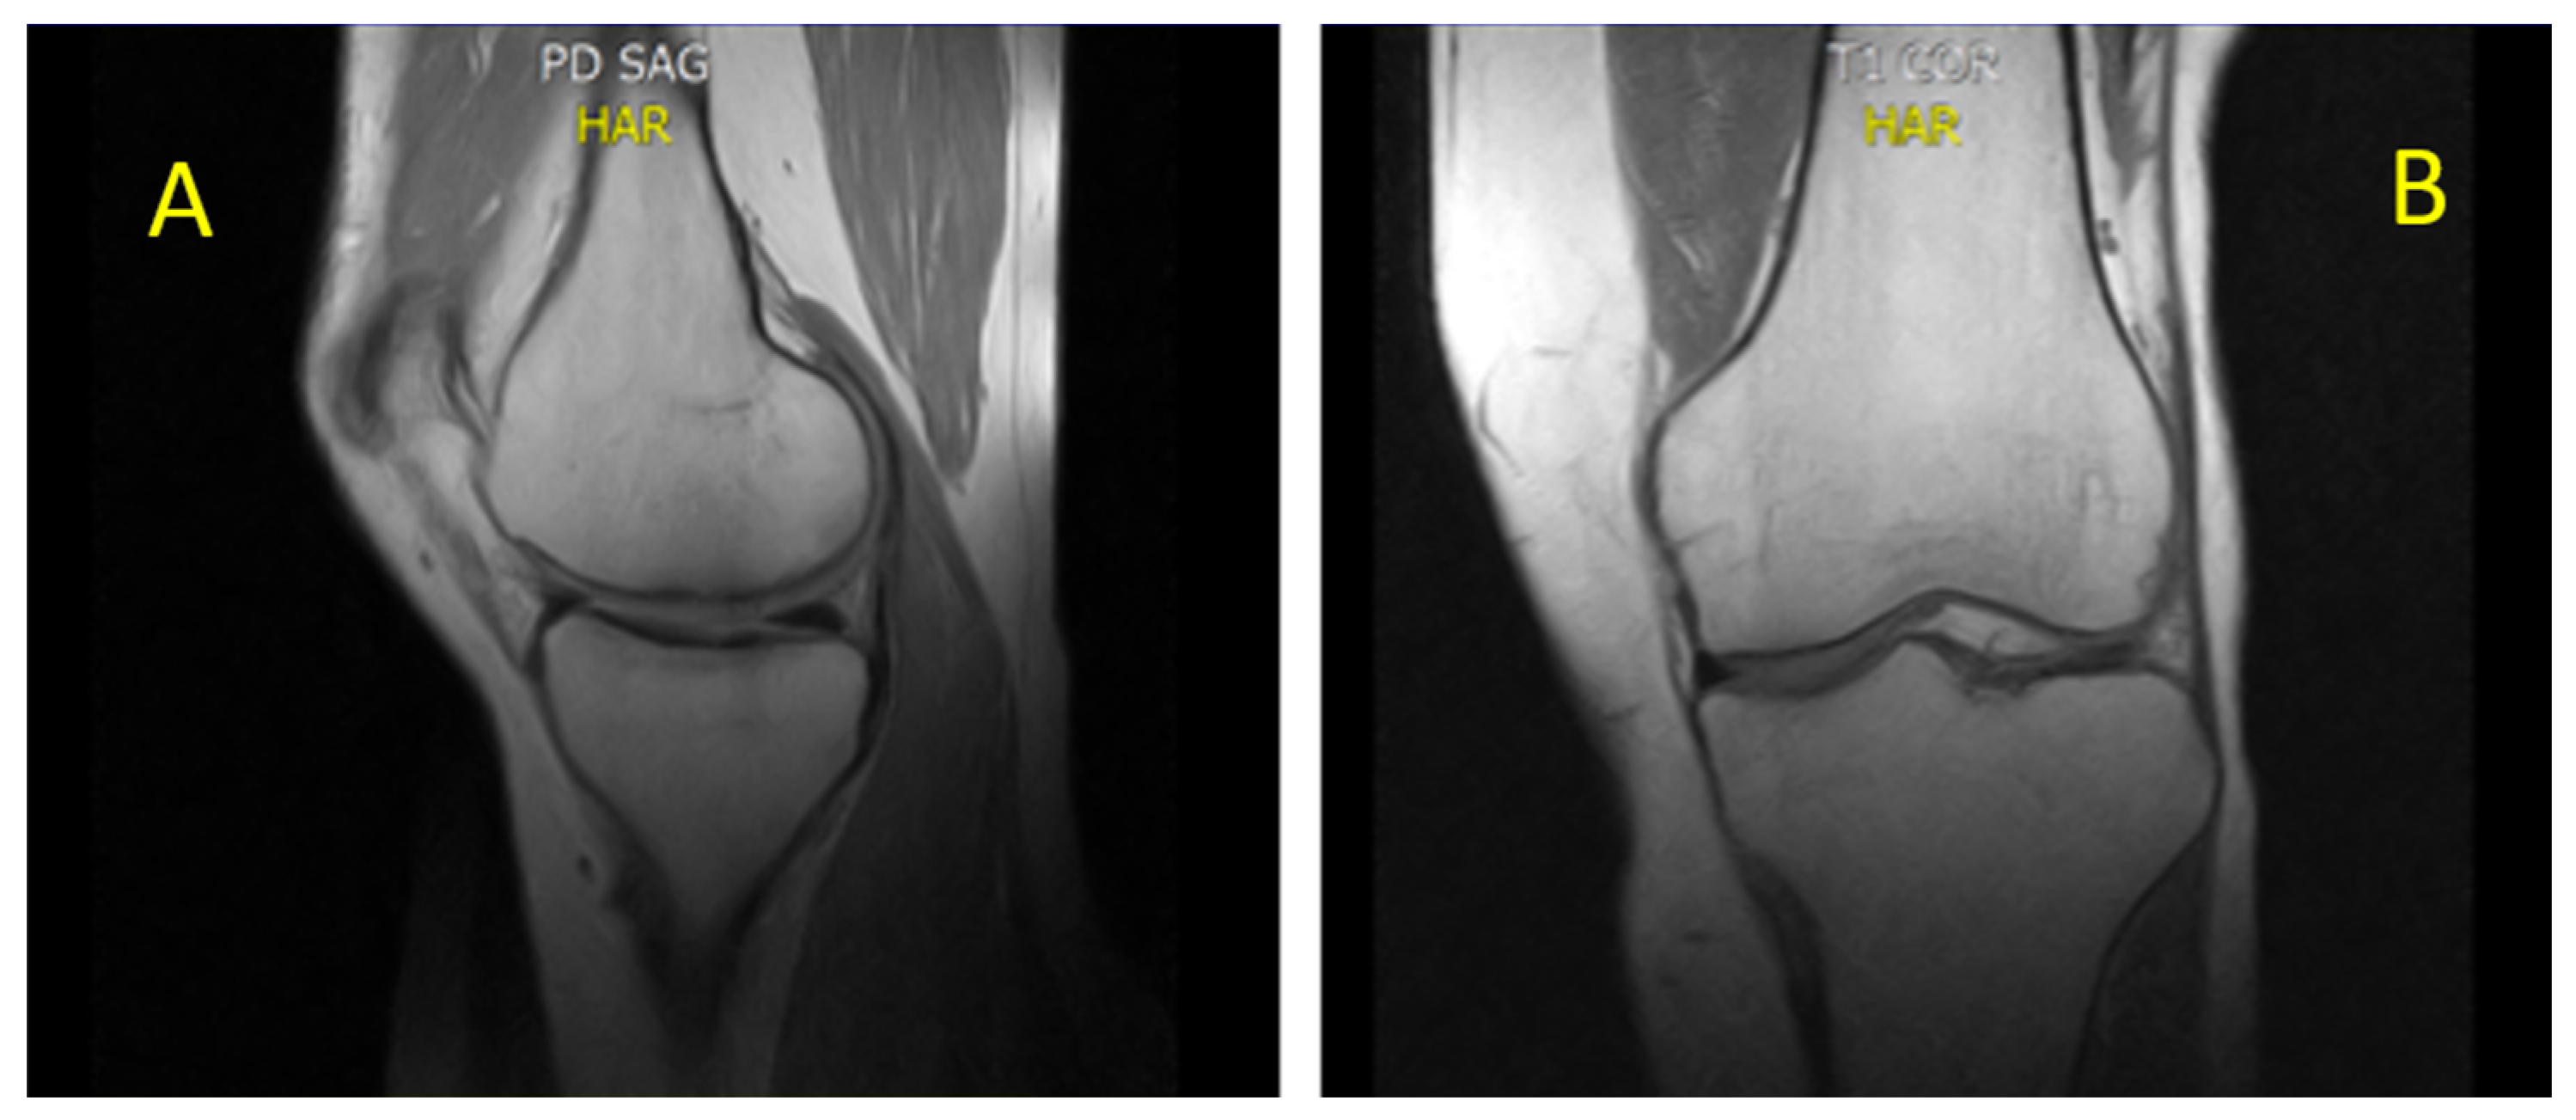

- CASE 1: A CML patient under dasatinib and imatinib treatment

- CASE 2: 60-year-old patient with imatinib therapy

- CASE 3: 66-year-old patient with imatinib therapy